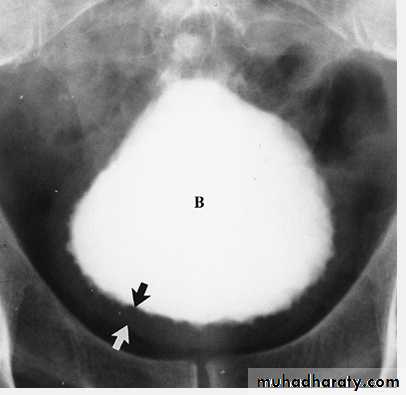

Bladder rupture. A cystogram done in a patient after a motor vehicle accident shows extravasation of contrast (arrows) into the tissues surrounding the bladder, an extraperitoneal bladder rupture